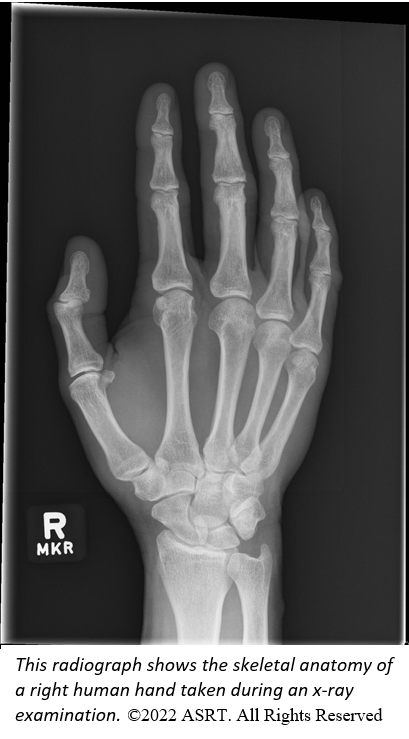

ALBUQUERQUE, N.M., Nov. 07, 2022 (GLOBE NEWSWIRE) -- Health care dramatically changed on Nov. 8, 1895, when German physicist Wilhelm Conrad Roentgen discovered the x-ray. Hailed as a medical miracle, scientists and physicians started using x-rays in the clinical setting soon after, and its use skyrocketed in the early 20th century. Fast-forward to 2022 and health care providers still rely on the x-ray to detect bone fractures, find foreign objects in the body, identify lung disease and much more.

A photo accompanying this announcement is available at https://www.globenewswire.com/NewsRoom/AttachmentNg/b5407d37-b815-413b-a054-c2ec4e10b8fe